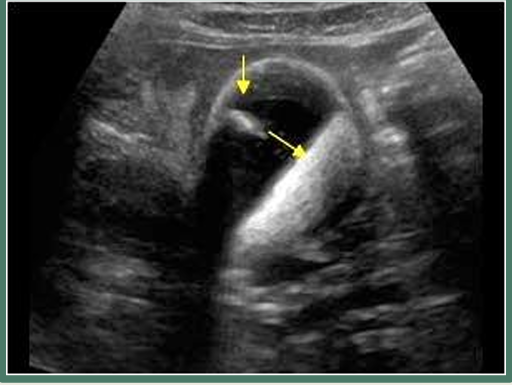

term image

cholelithiasis

WES sign